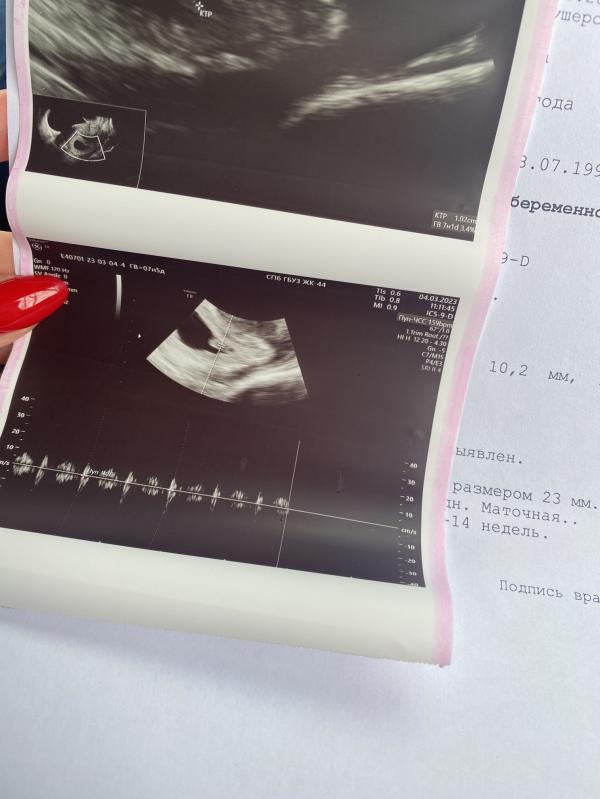

159 ударов в минуту)

Вчера была на узи, КТР 1 см